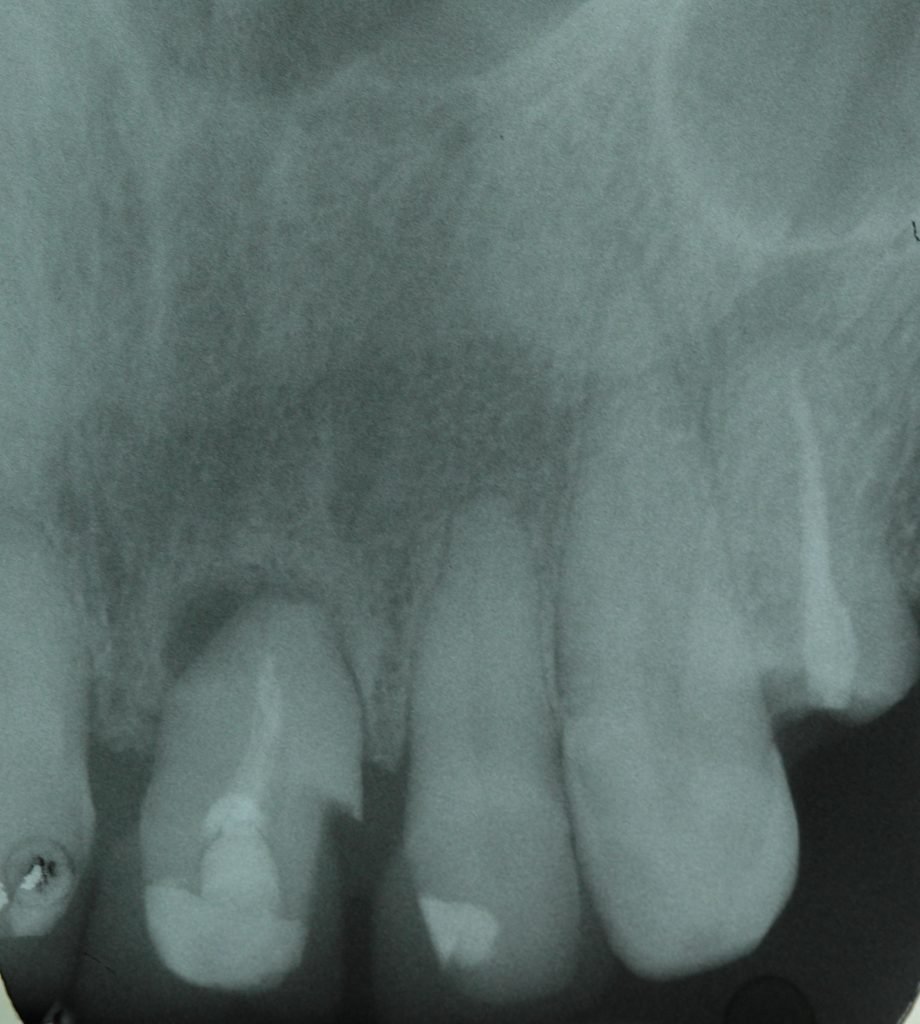

Punto Bajío Casos Clínicos Prótesis Fija sobre Implante unitario Inicio Provisional Final Prótesis Parcial Fija sobre 2 Implantes 2 Implantes Final Prótesis Bucal Removible Inicial Inicial Superior Inicial Inferior Rayos X Inicial Rayos X Inicial Frontal Final Final Superior Final Inferior Prótesis Parcial Fija/ Coronas de Circonio Sonrisa Inicial Foto Inicial Foto Inicial Inferior Foto Final Inferior Foto Final Sonrisa Final Prótesis Total Protesis Inmediatas 1 Protesis Inmediatas 2 Prótesis Removible/ Coronas Metal-Ceramica Carillas Incrustaciones Endodoncia